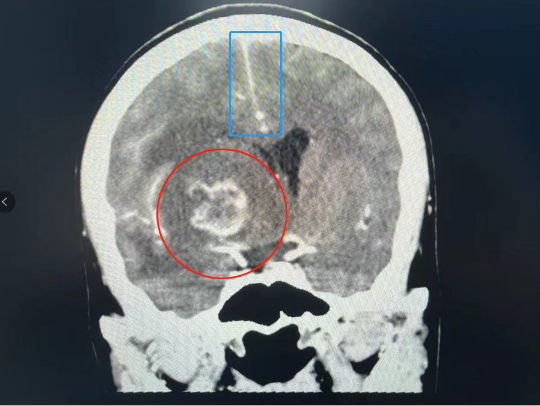

红圈内是颅内病灶 蓝框内是脑中线

在持续头痛4天以后,家住深圳的高女士终于忍不住去了医院,此前她已经反复头痛一年有余。很快她收到一个惊人的噩耗:她竟然查出了HIV阳性,而且颅内有一处较大的占位性病变,已经导致大脑中线明显偏移!

在医生的建议下,高女士转入了深圳市三医院感染与免疫科。感染与免疫科主任医师周泱介绍,艾滋患者的颅内病变通常症状不典型、影像学结果没有明显特异性,因此很难直接判断究竟是什么导致了病变,唯一的“金标准”是脑活检的病理检查结果。